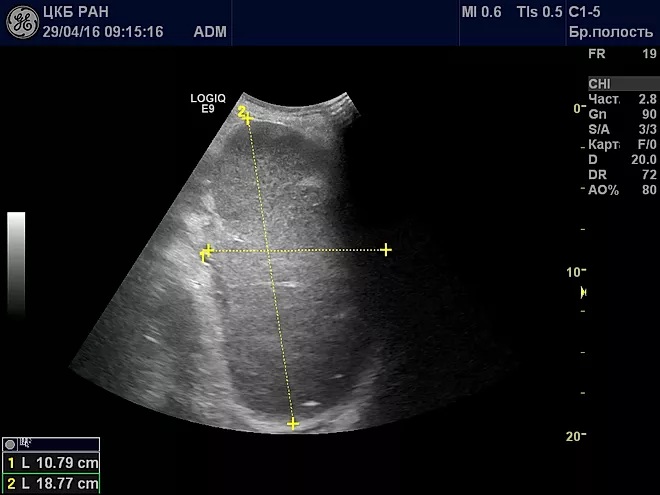

- Ультразвуковое исследование (УЗИ). С его помощью можно выявить внешние изменения органа — размер и форму. Также хорошо показывает наличие травм, аномальных признаков развития, воспалений и опухолей.